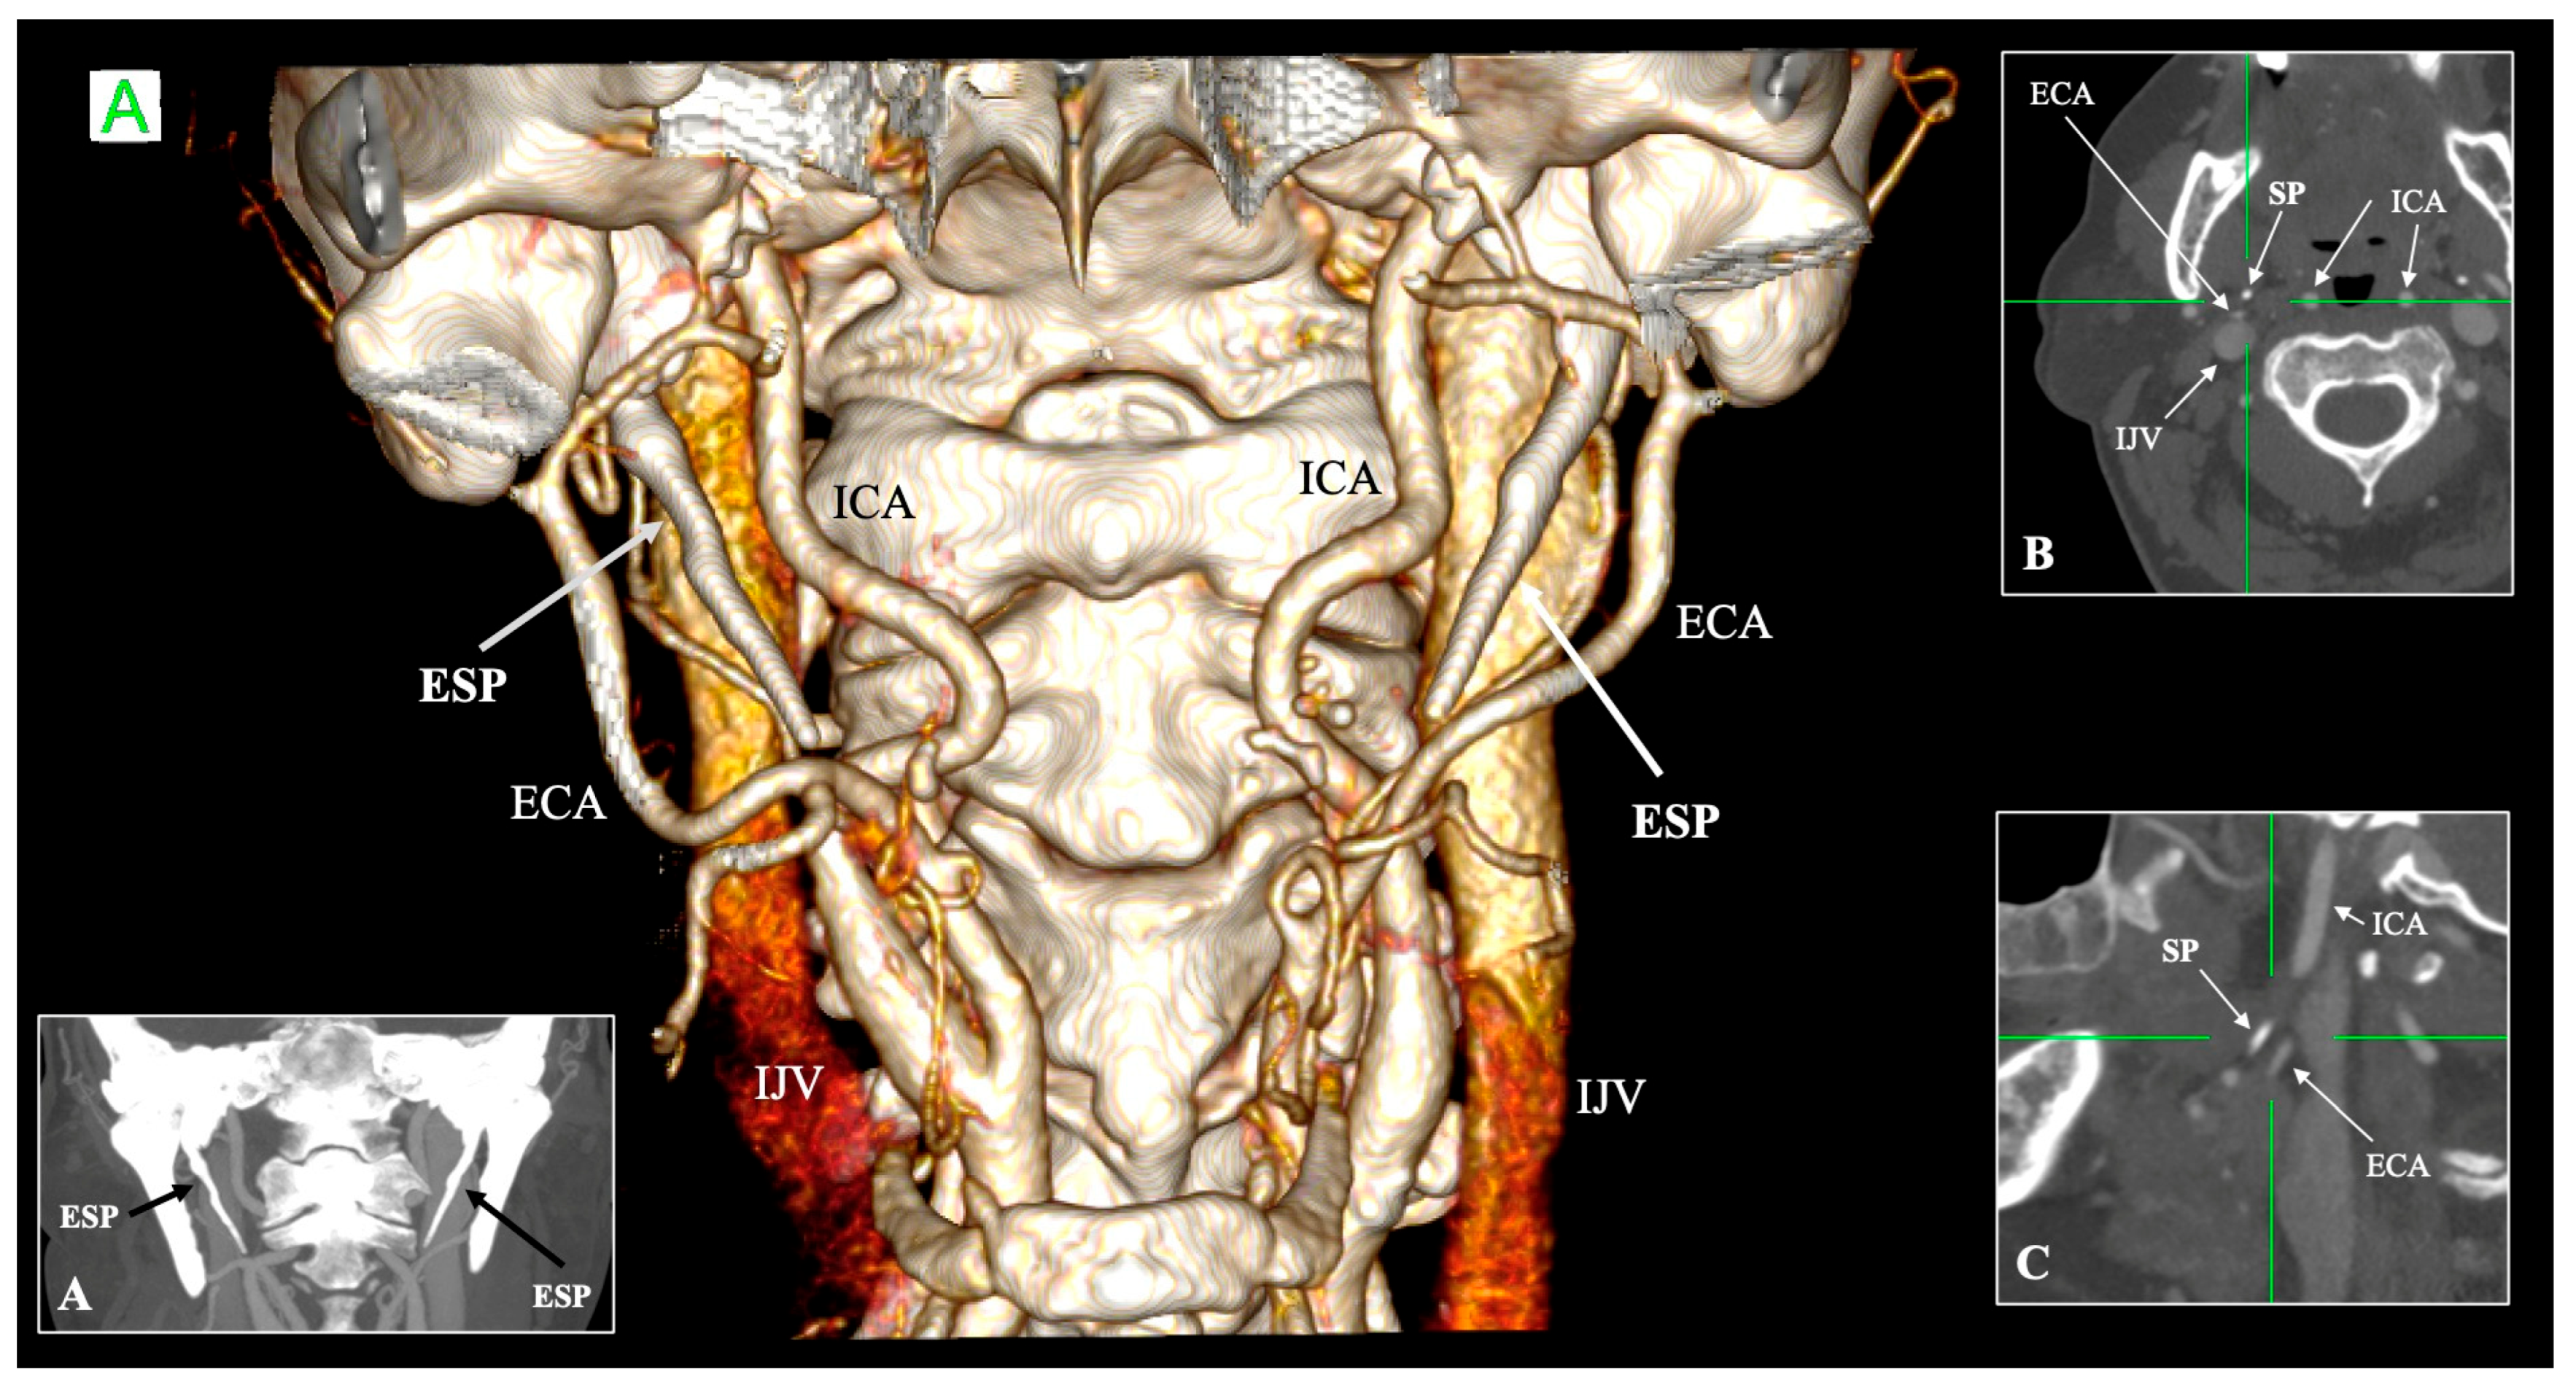

4.5. Relationship with Neurovascular Structures

| External carotid artery (ECA) | Anterolateral to SP; gives facial and pharyngeal branches | Retro-styloid course (~9–12%) | Altered surgical corridor; potential compression or irritation | Karangeli et al. [17]; Calotă et al. [50] |

- Calotă, R.N.; Rusu, M.C.; Vrapciu, A.D. The External Carotid Artery and the Styloid Process. Curr. Health Sci. J. 2024, 50, 232–236. [Google Scholar] [CrossRef] [PubMed]